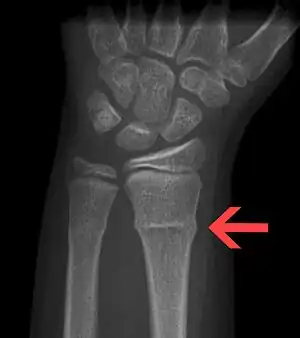

| X-ray of a torus fracture involving the distal radius | |

Buckle fractures can generally be identified by X-ray. The diagnosis is made from both anterior/posterior and lateral projections. The typical features include:

- The buckling of cortical bone, which may appear as a small bulge or protuberance in the radius or ulna.

- The bone may have a slight angulation.[9]